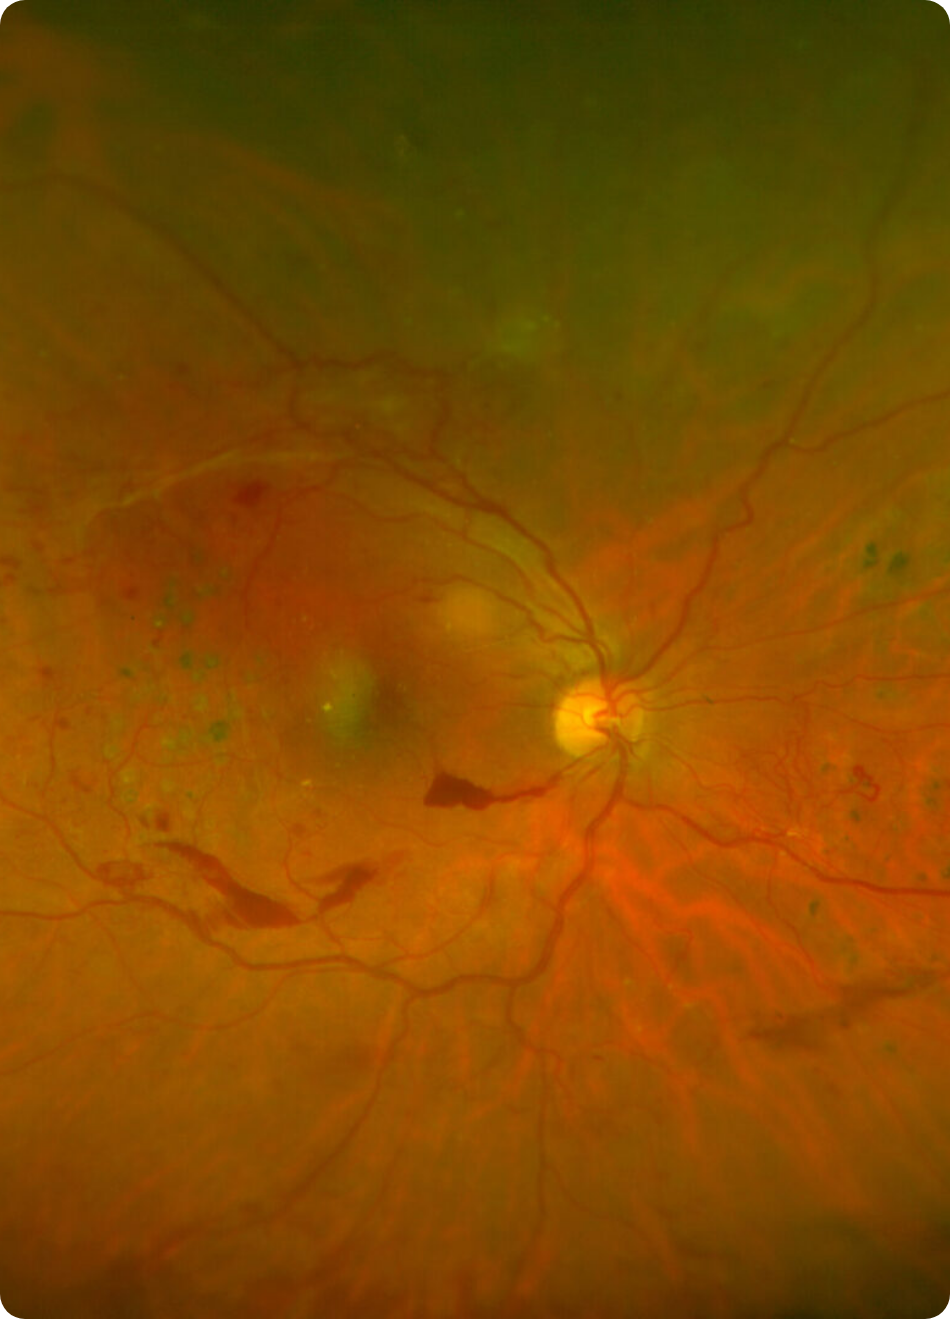

En algunos pacientes el daño a los vasos sanguíneos puede ser tal, que pueden llegar a acumularse líquido y proteínas en la mácula (es decir, la parte central de la retina), causando algo conocido como edema macular, causando disminución importante de la visión.

Si el daño a la retina continúa, aparecen en la retina vasos sanguíneos nuevos (conocidos como neovasos), cuya intención es llevar más oxígeno y nutrientes a la retina, pero que en realidad sólo sirven para causar las complicaciones de la enfermedad que pueden poner en riesgo la visión de manera permanente. Cuando aparecen estos vasos anormales, la retinopatía diabética se conoce como proliferativa.

Estos neovasos pueden romperse, causando una hemorragia vítrea, es decir, que la sustancia transparente que rellena el ojo llamada humor vítreo se manche de sangre, causando disminución súbita de la visión.

Estos mismos neovasos pueden causar un desprendimiento de retina, o si crecen en la parte anterior del ojo, pueden causar glaucoma neovascular.